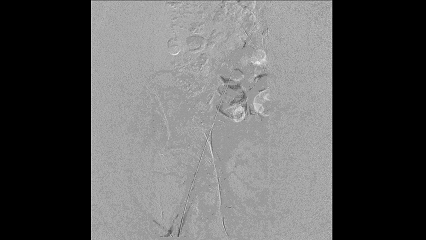

最终结果

最终造影证实血流通畅,管腔获得满意,远端无栓塞证据。